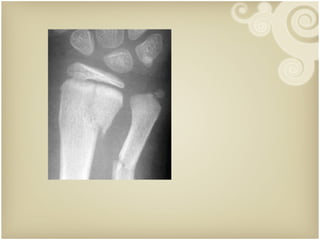

Law of Two’s  : Two views Two joints Two limbs Two occasions Two physicians Xray examination   2